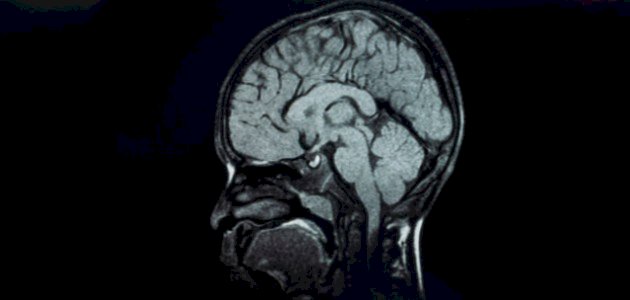

يُعد التصوير بالرنين المغناطيسي للدماغ (MRI) أحد الطُرق الرئيسية لتشخيص ضمور المخيخ، تليه الاختبارات خزعة العضل، ودراسة الجهاز العصبي المحيطي للطفل المُصاب،[٤] كما قد يوصي الطبيب بفحوصات أخرى تتضمن ما يأتي: